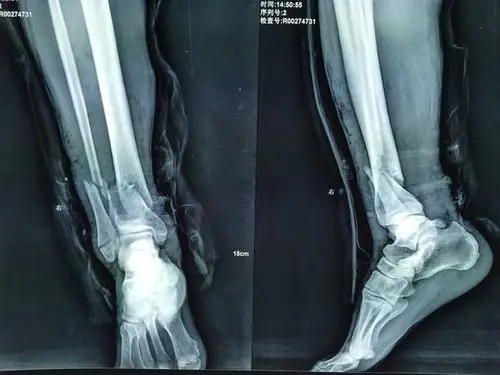

右胫腓骨远端骨折